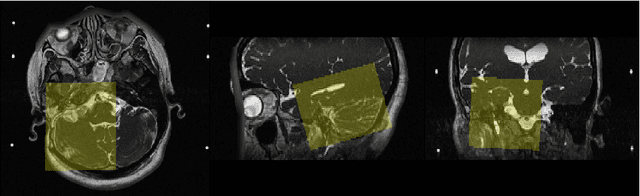

Automatic methods to segment the vestibular schwannoma (VS) tumors and the cochlea from magnetic resonance imaging (MRI) are critical to VS treatment planning. Although supervised methods have achieved satisfactory performance in VS segmentation, they require full annotations by experts, which is laborious and time-consuming. In this work, we aim to tackle the VS and cochlea segmentation problem in an unsupervised domain adaptation setting. Our proposed method leverages both the image-level domain alignment to minimize the domain divergence and semi-supervised training to further boost the performance. Furthermore, we propose to fuse the labels predicted from multiple models via noisy label correction. In the MICCAI 2021 crossMoDA challenge, our results on the final evaluation leaderboard showed that our proposed method has achieved promising segmentation performance with mean dice score of 79.9% and 82.5% and ASSD of 1.29 mm and 0.18 mm for VS tumor and cochlea, respectively. The cochlea ASSD achieved by our method has outperformed all other competing methods as well as the supervised nnU-Net.